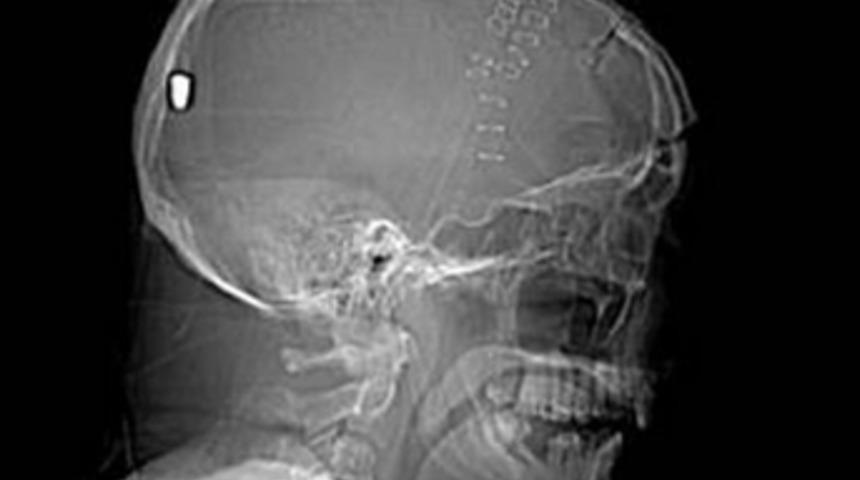

Kafatasına saplanan merminin gizi çözülemedi!

Ancak çekilen röntgen sonrasında, Hesford'un beynine bir mermi saplandığı ortaya çıktı.

19 Nisan'da meydana gelen olayın ardından Hesford'un kafasına bir objenin saplandığını farkeden ilk yardım ekipleri, onu hastaneye kaldırmış, hastanede de kafasındaki cismin mermi olduğu anlaşılınca polise haber verilmişti.